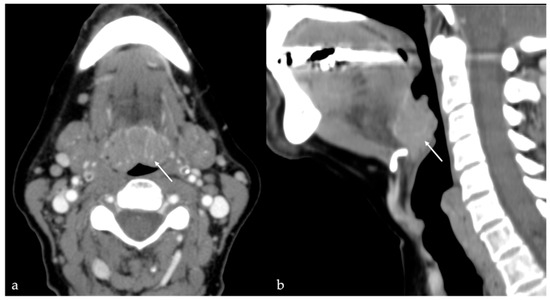

7.1. Thyroglossal Duct Cyst

| Thyroglossal duct cyst [15] Ectopic thyroid tissue [16] | Cyst Same features as thyroid tissue | Lingual tonsil mucous retention cyst Squamous cell carcinoma and lymphoma of the tongue base |